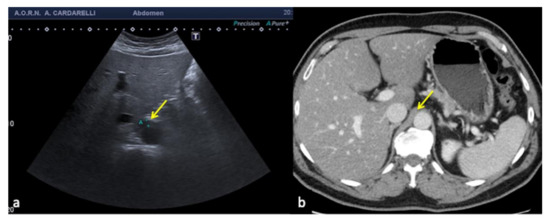

3.4. Anatomy and Anatomical Variants

Some anatomical structures and variances might yield difficult-to-interpret pictures, which can lead to errors if not fully understood [6]. The most insidious in emergency situations are pseudo-splenic hematoma (Figure 16 and Figure 17), pseudo-collections of pleural, pericardial, peritoneal, and retroperitoneal fluids (Figure 18, Figure 19, Figure 20 and Figure 21), and pseudo-pneumothorax related to abolished lung sliding due to the lung pulse or to patient apnea [6,7]. Others, such as hypertrophy diaphragmatic pillar (Figure 22), bladder pseudo-masses (Figure 23), inguinal pseudo-hernias (Figure 24), and the rouleaux phenomena, are generic, random, and highly conditioned (Figure 25). Often it is the emergency condition of the clinical context itself as well as the traumatic accident that could influence interpretational doubts or over-diagnosis with the necessity of more diagnostic confirmations, involving more costly complex examinations, an increased waiting time for the final diagnosis and medico-legal disputes [3,13].

Figure 19. Longitudinal US left flank scan (a) shows at the lower pole of the kidney (K) a hypoechoic area which may be misinterpreted as retroperitoneal free fluid (arrows) in a 22-year-old man investigated for trauma. On CT scan (b) it appears to be a spastic intestinal loop (arrow).